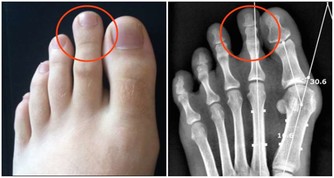

1.中指指甲凹陷:體內尿酸過多、肌肉痠痛。